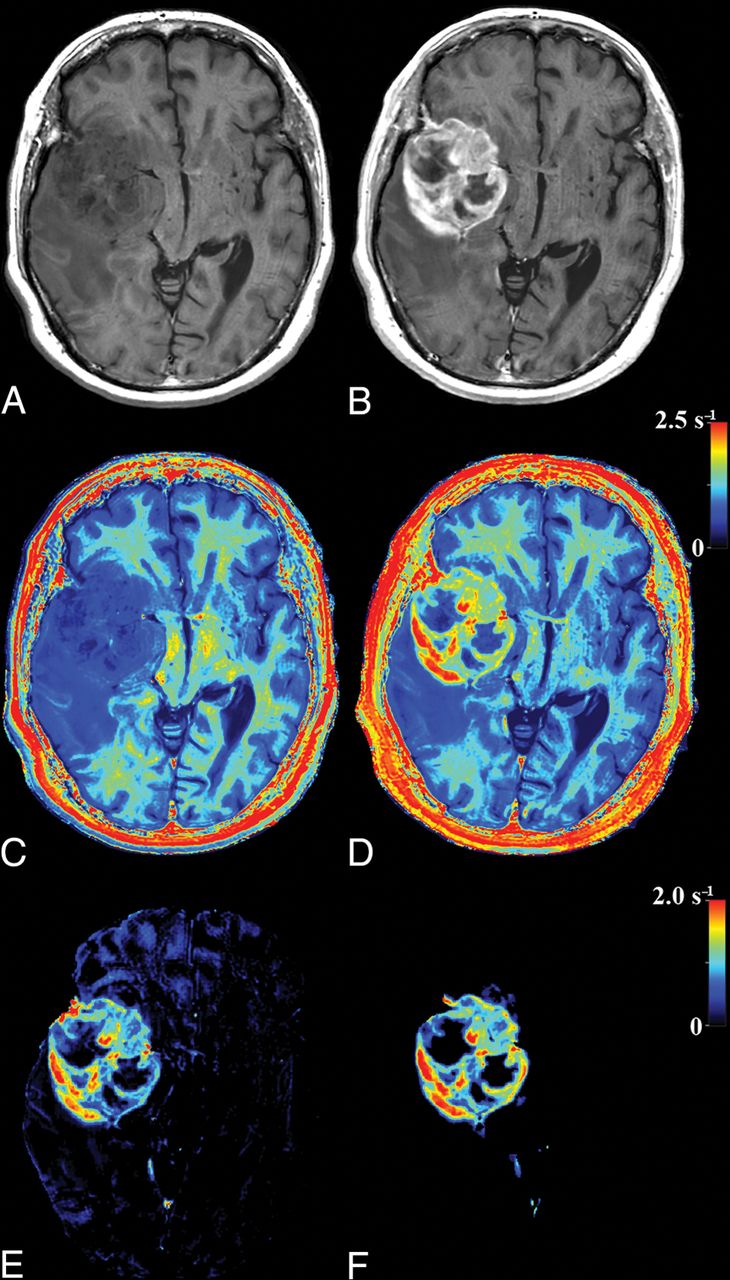

In Fig 4, the tumor in Fig 2 is zoomed-in. The native and post-GBCA T1-weighted images are shown as well as the ROI drawn by the radiologist. In Fig 4D, the synthetic R1 enhancement map is shown as a green overlay where full color corresponds to a dR1 of 1 second−1. At various places, low-intensity enhancement in the range 0.2–0.5 seconds−1 is observable outside the high-intensity enhancing tumor and drawn ROI. On average for all patients, 35.8% of the pixels touched by the drawn ROI lines had values above 0.2 seconds−1 for the synthetic R1 enhancement map and even 50.3% for the subtraction R1 enhancement map. When the ROI line was expanded with an additional margin of 1 or 2 mm, this percentage reduced to 8.0/17.4% and 2.3/8.6%, respectively (Table 2).

Zoomed part around the tumor displayed in Fig 2. Synthetic T1-weighted imaging using native data (A), synthetic T1-weighted imaging using post-GBCA data (B), the ROI line as drawn by a neuroradiologist to encapsulate the border of the enhancing tumor (C). D, Synthetic R1 enhancement map shown as a green overlay on the synthetic T1-weighted image in which full color corresponds to dR1 = 1.0 seconds−1. The minimum enhancement was set at dR1 = 0.2 seconds−1. Some low-intensity enhancement is visible outside the yellow ROI. The red line indicates the edge of the intracranial volume.

In 10 of 14 patients, >1 mL of tissue was found in the synthetic R1 enhancement images with an enhancement of >0.2 seconds−1 outside the drawn ROI. The mean additional tumor volume for all patients was 1.71 ± 1.28 mL, with a maximum of 4.3 mL. In comparison, the mean tumor volume within the ROIs was 63.5 ± 44.4 mL (range, 9–134 mL). More examples of the synthetic R1-enhancement maps are provided in Fig 5.

Other examples of the synthetic R1 enhancement map and low-intensity enhancement at the edges of high-intensity enhancement in gliomas. Left: native synthetic T1-weighted image. Center: post-GBCA synthetic T1-weighted image. Right: synthetic R1 enhancement map as a green overlay. The color indicates a range of dR1 of 0.2–1.0 seconds−1. The red line indicates the edge of the intracranial volume.